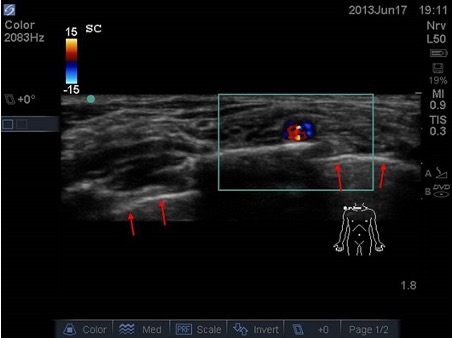

- Identify targets (nerves, fascial planes) – example 1, median nerve to the forearm

- Identify nearby structures (blood vessels, bowel, bone, pleura) which allows you to avoid complications (especially in small children where target structures and nearby structures are in immediate proximity or very superficial) – example 2, supraclavicular plexus in neonate: very little space between plexus, vessels, pleura, ribs.